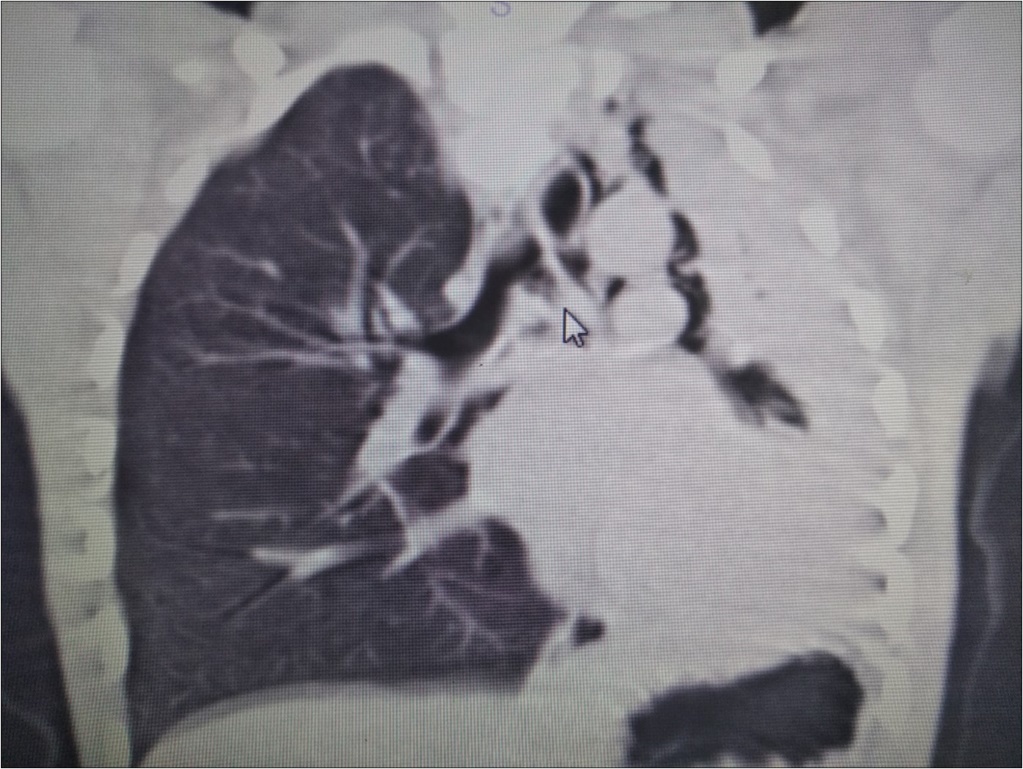

A 6 year-old boy was admitted to our hospital with the symptoms of upper respiratory tract infection (URI). He had hemoptysis 2 days prior to admission to hospital. On admission he had respiratory distress, fever (39°). Plain chest graphy demonstrated a complete opacification of the left lung (Figure 1). Thorax ultrasonography was normal and high resolution computed tomography (HRCT) of the chest revealed a 50-60% narrowing of the left main stem bronchus starting from carina downwards (Figure 2). Although there was no history of foreign object aspiration an emergent bronchoscopy was performed for a possible unnoticed aspirated foreign body. A bronchial cast located at the carineal bifurcation of trachea measuring 3x1 cm was detected and easily removed with forceps during bronchoscopy (Figure 3). The material was whitish, rubbery in consistency. Histopathologic examination of the cast revealed that it consisted of condensed fibrin, neutrophils and eosinophils. Culture was also obtained from the specimen for a possible bacterial growth. Following bronchoscopy the patient required mechanical ventilation for ventilatory support in the mode of high frequency oscillatory ventilation (HFOV) with supplementery oxygen in intensive care unit (ICU). In his 3rd hospital day, control chest graphy of the child showed complete opacification of the left lung and for a chance of residual cast in the tracheobroncial tree a repeat bronchoscopy was performed. Two seperate casts from the left main stem bronchus measuring 1.5x1 cm and 2x1 cm in length were removed with forceps and lavage with aspiration of both right and left main stem bronchus was performed. Following second bronchoscopy the transcutaneous oxygen saturation increased from 77 to 99 and control chest roentgenogram showed equal expension of both lungs. While in his stay in ICU, in addition to mediacal treatment, respiratory physiotherapy was performed regularly. He was medically treated with aerosolized dexamethasone with adrenalin. Bacterial test obtained from cast was found positive for Streptococcus viridans and vancomycin was started. On his 5th day in ICU, his respiratory status worsened and a chest graphy showed a decrease in expension of the left lung and a control bronchoscopy was performed. In this third bronchoscopy trachea and both right and left main stem bronchus were found to be patent but were found to have excessive viscous secretions. Pulmonary toilet including lavage and aspiration of thick tenacious secretions was performed. On day 12 he was transferred from the ICU and 1 week later he was weaned off the ventilator. He underwent pulmonary rehabilitation. During his 3rd year of follow up he has no further episodes of respiratory distress and he is disease free.

Figure 2.HRCT of the patient showing narrowing of the left main stem bronchus starting from carina downwards.

Radiographic findings are nonspecific and include atelectasis secondary to airway obstruction, hyperinflation due to air trapping, unilateral opacification, as seen in our case, bronchiectasis and lung infiltrates. It has been reported that HRCT may allow in some cases the visualization of bronchial casts in the airways of larger caliber 19. However the gold standard in diagnosing PB is bronchoscopy which reveals the airway obstruction by BC 3.